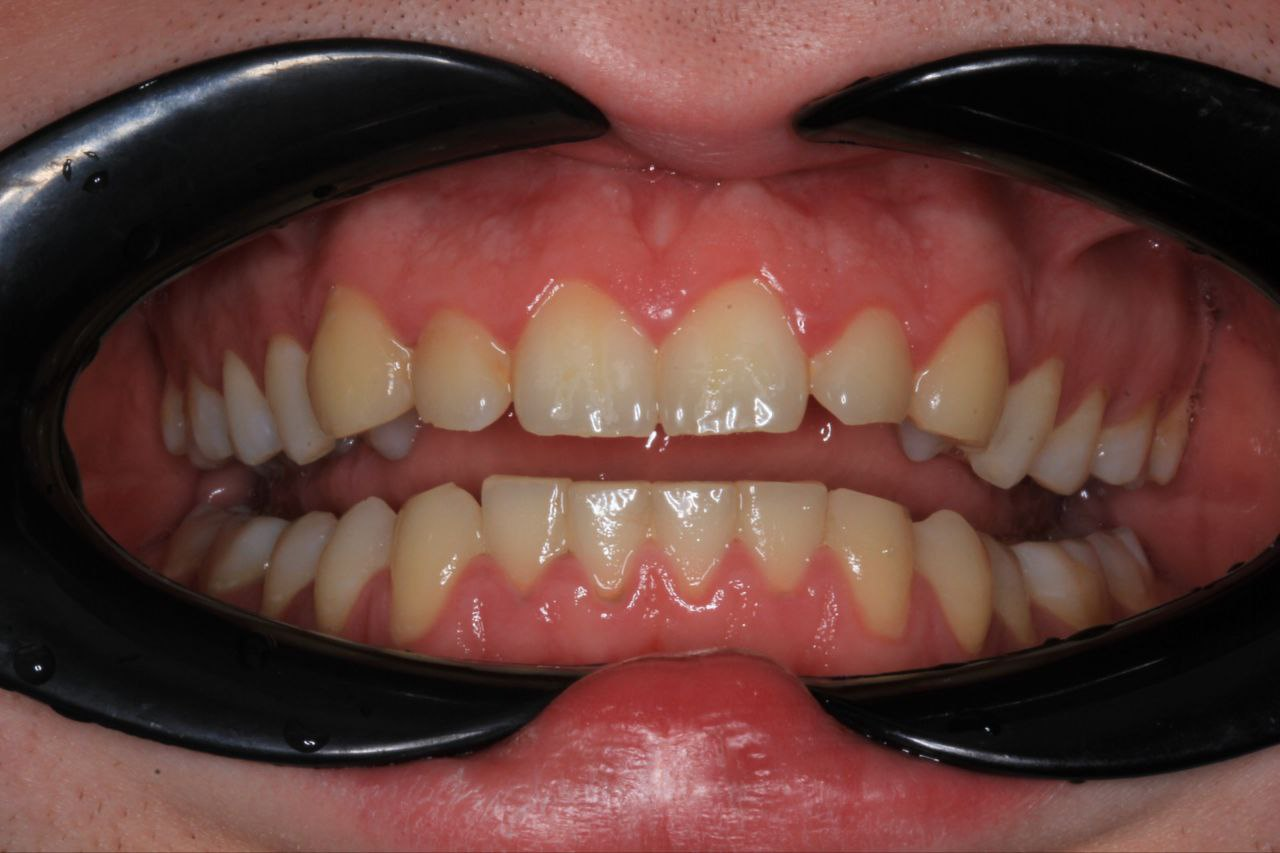

мезиальный прикус, пара зубов на верхней челюсти стоит 2 рядом при этом зубы мудрости сверху выросли нормально

какие шансы просто поставить брекеты и обойтись без операций?

а главный вопрос - по чём сейчас брекеты?

Мне вот зубы мудрости, правда ретинированные, удаляли как раз перед брекетами. Зубы мудрости крупные и сдвигают зубы другие, скучивая их.

Чаще всего рекомендуют их удалить. Потому что после исправления прикуса не факт что зм не поднасрут опять.

По цене у меня в миллионнике так

3д цефалометрия 7к.

Сложное удаление одного зуба 11к. Обычный дешевле будут.

Брекеты и их установка 150к.

Прием перед брекетами и слепок зубов хз сколько.

Посещение 2-4к раз в 2 месяца.

Снятие хз сколько. Ретейнер и или капа на ночь хз.

В любом случае сами брекеты, 150к, это основная сумма. Остальное по мелочи.

В дс 4 выйдет в 2 раза дешевле. Сестра вместо 150 отдала 70 за такие же.